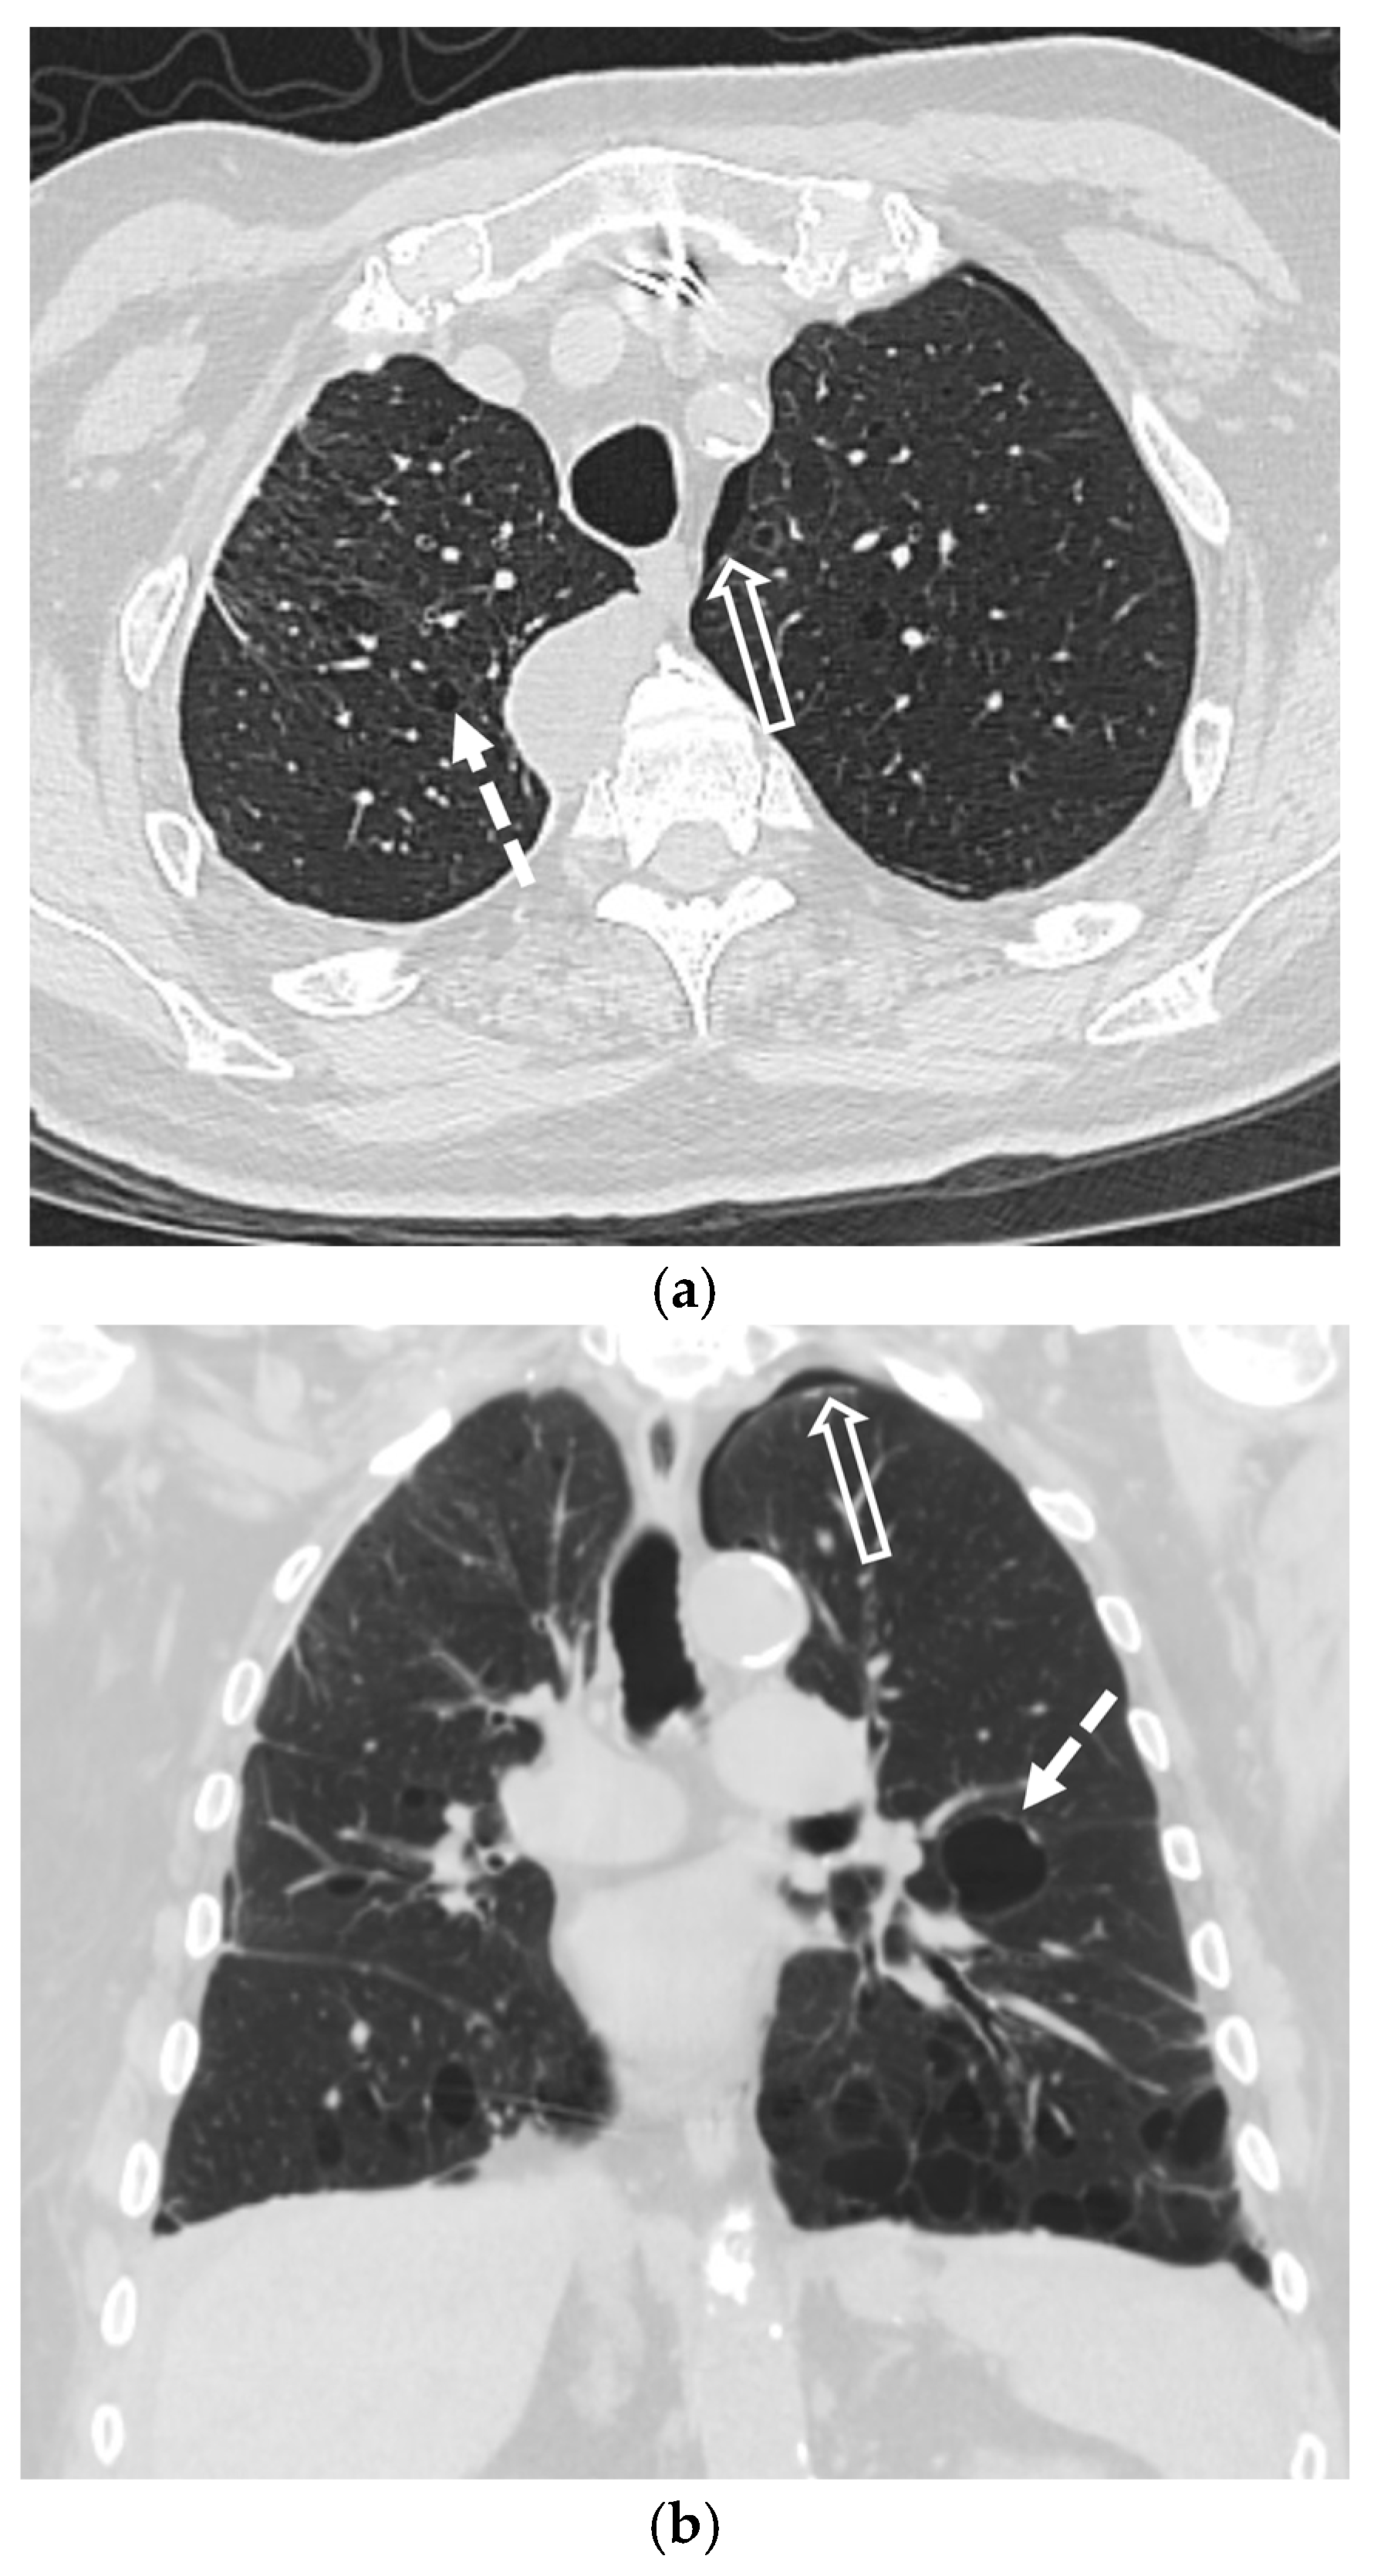

5.4. Interstitial Lung Diseases (ILDs)

5.4.1. Idiopathic Pulmonary Fibrosis (IPF)

5.4.2. Lymphoid Interstitial Pneumonia (LIP)

5.4.3. Sarcoidosis

3.3. Computed Tomography (CT)